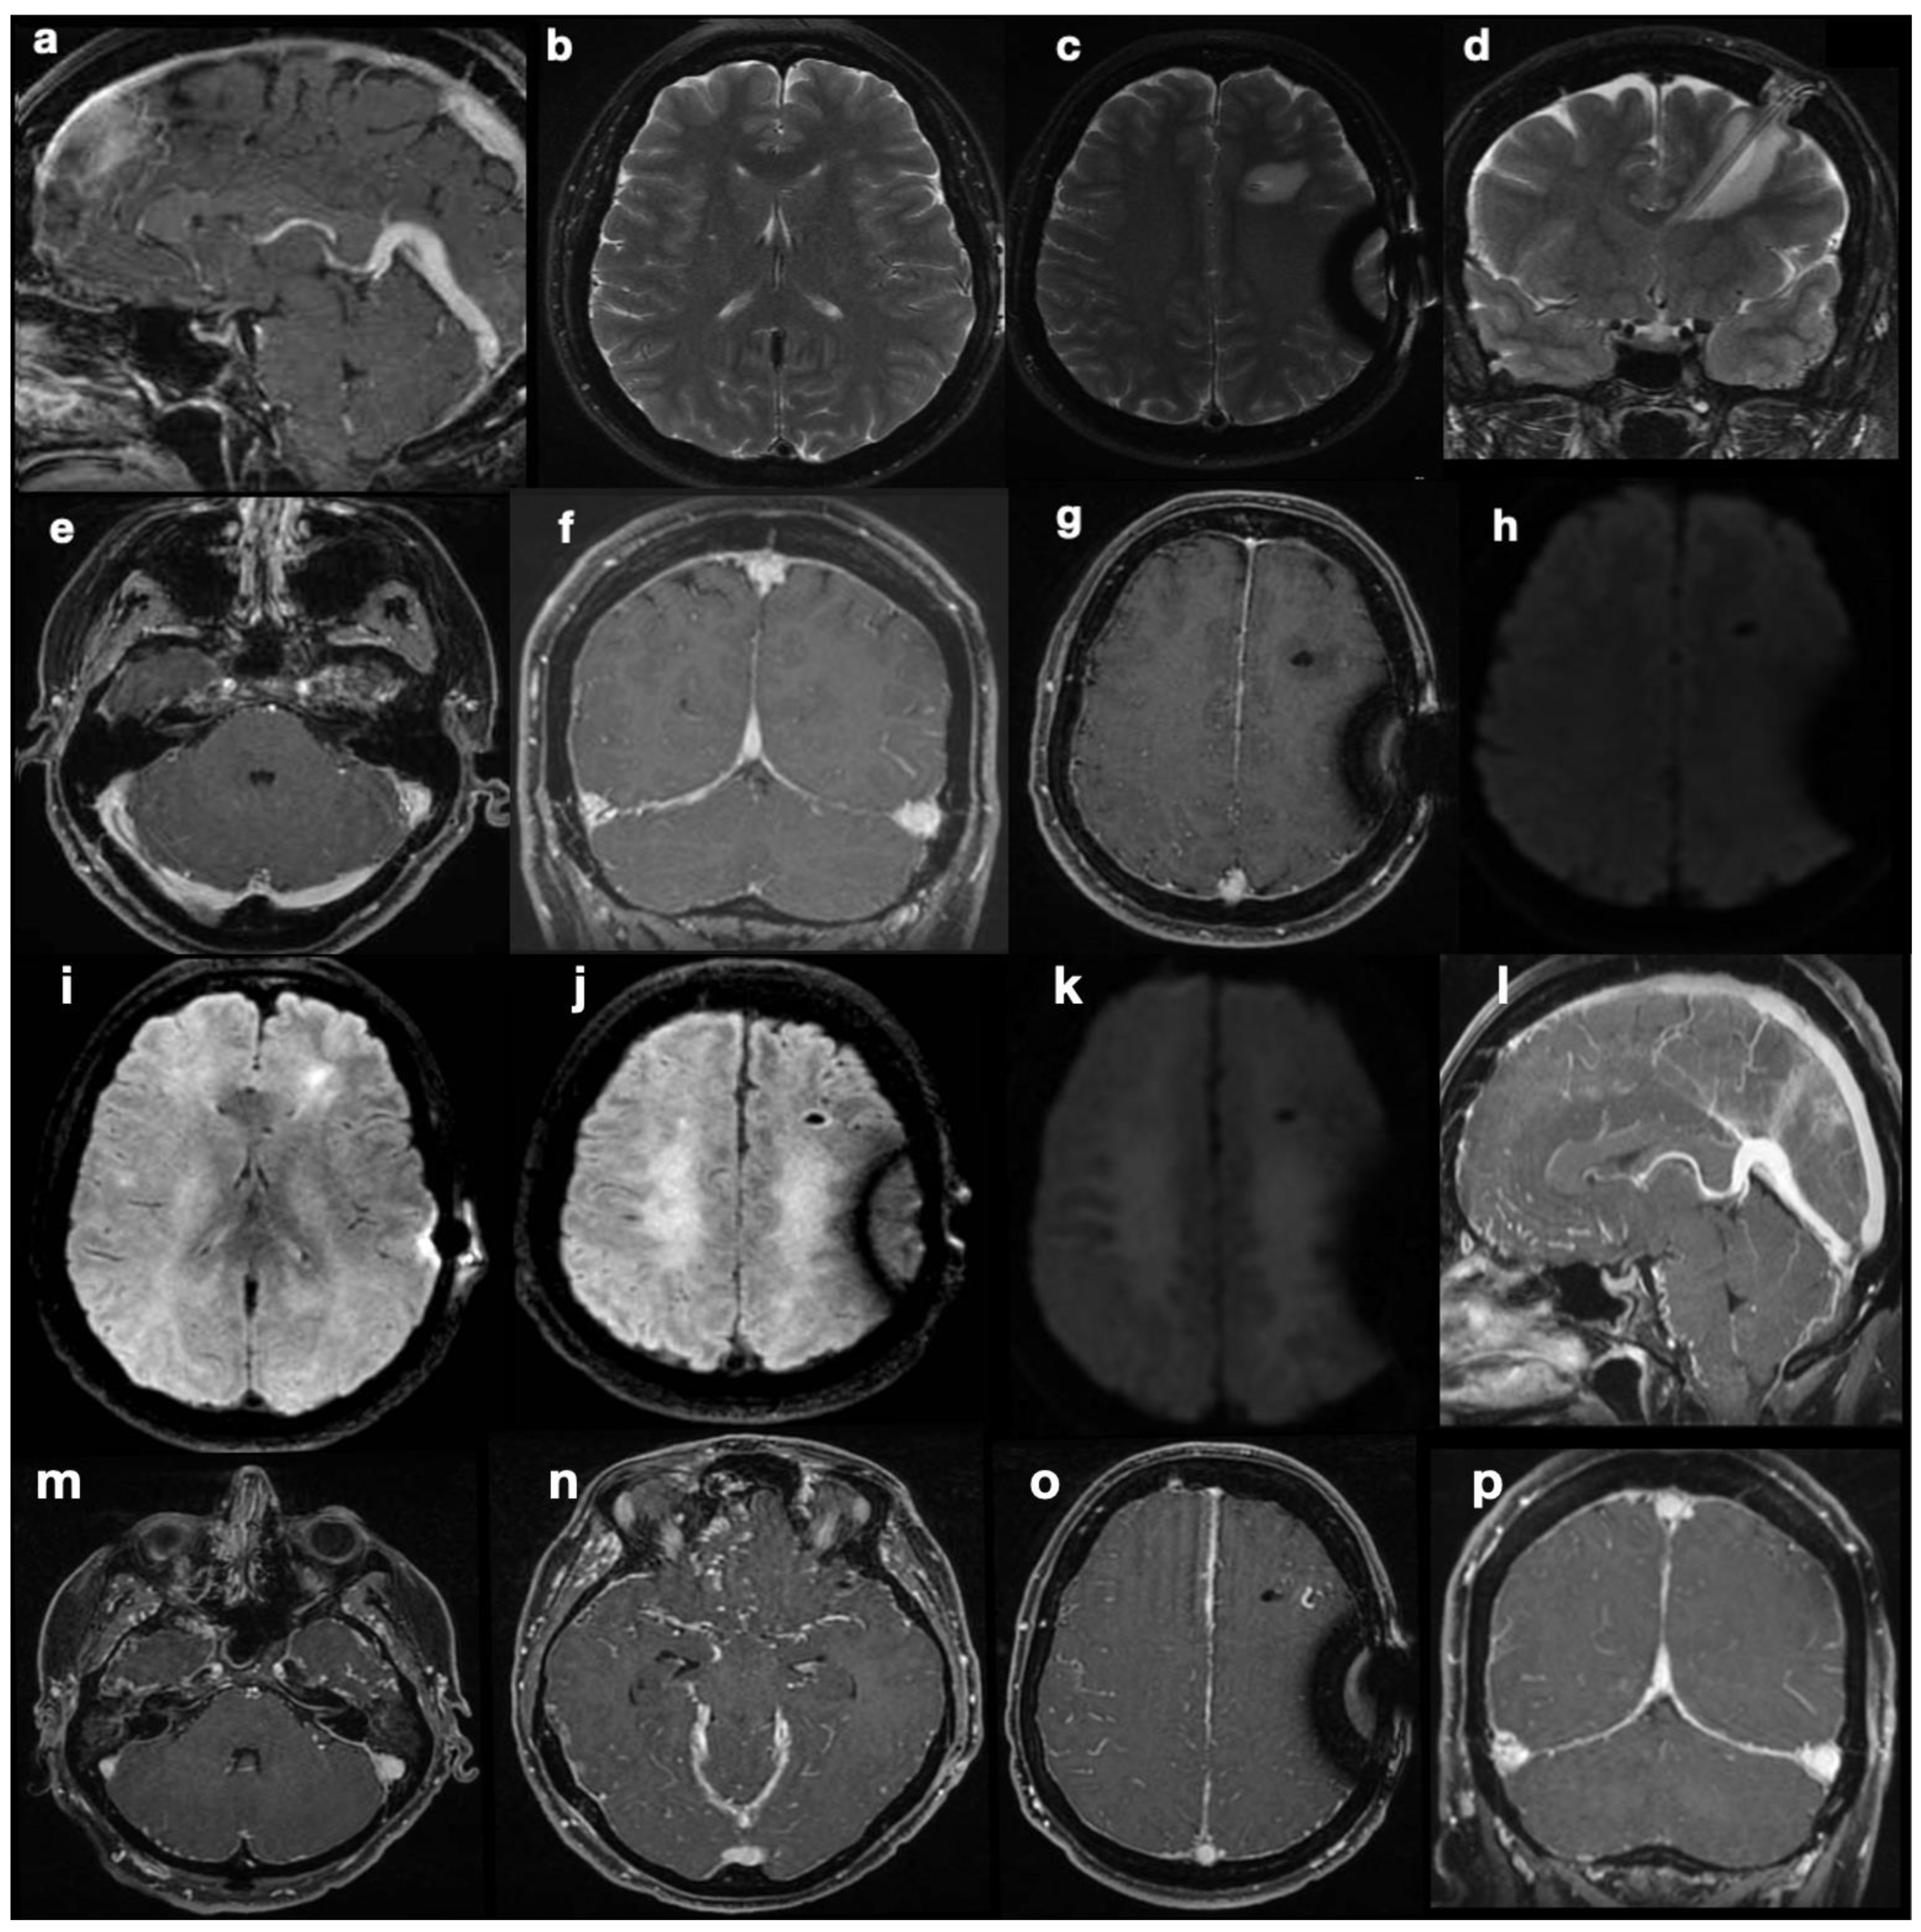

Upon her admission to our hospital, an MRI exam was repeated with contrast media administration. On T2WI, the fourth ventricle was markedly enlarged (Figure 3a and Figure 4a), compressing the pons anteriorly and the cerebellum posteriorly. Accordingly, subtentorial cisterns were effaced. A thin diaphragm was appreciable within the acqueductus Silyii. Axial scans of the enlarged fourth ventricle showed patent and enlarged foramina of Luschka (Figure 3a). T2W hyperintensities in the ventricle walls and around the cranial portion of the central canal suggested trans-ependymal reabsorption and incipient hydromyelia (Figure 4b,c). The MRI exam showed caudal dislocation of the bulbo-medullary junction and herniation of cerebellar tonsils through the foramen magnum. On the other hand, T1W C+ scans showed a diffuse enhancement of the thickened dura mater, surrounded by hyperintense epidural spaces (Figure 4b).

The patient was then diagnosed with isolated dilatation of the fourth ventricle, caused by overdrainage from the SPS causing downward tonsillar displacement as the origin of IV ventricle intracranial and spinal hydrocephalus. The increase in the SPS valve-opening pressure, with subsequent downregulation of the shunt, led to prompt symptom regression and the disappearance of hydromyelia and other MRI signs of trans-ependymal reabsorption (Figure 4e,f).

Isolated dilatation of the fourth ventricle is a rare complication of ventriculoperitoneal shunt surgery, with it being most frequent among pediatric patients and poorly characterized in adults [16,17]. Necessary conditions are, typically, obstruction of the foramina of Luschka and Magendie, inferiorly, and the aqueduct of Sylvius, superiorly. In our case, congenital aqueductal stenosis was present (Figure 4a,d), but foramina were apparently patent—even symmetrically dilated (Figure 3a), while the site of obstruction was farther below. SPS overdrainage caused brainstem and tonsillar sagging, foramen magnum obstruction, and CSF flow trapping in the posterior fossa. Thus, the central canal became the only outflow route available, communicating with the high-pressure closed compartment of the fourth ventricle. Below the foramen magnum, a radial pressure gradient was present from the central canal (abnormally increased pressure) to the spinal subarachnoid space (abnormally decreased pressure). Conspicuous trans-ependymal reabsorption was then provoked in the spinal cord (Figure 4c), at risk of further extension with involvement of the brainstem. The therapeutic approach consisted of only modifying the drainage pressure of the shunt, thus increasing peri-medullary space pressure to normal levels and removing the CSF trapping in the posterior fossa. In turn, this reduced the pressure in the fourth ventricle and removed the gradient established between the central canal and the medullary sub-arachnoid space. The patient’s symptoms rapidly alleviated, without more invasive interventions being required. In subsequent MR examinations, further ascent of cerebellar tonsils was observed, with further resolution of fourth ventricle isolation. Nevertheless, long-term follow-up is needed to monitor the occurrence of late complications, including relapse of overdrainage with spinal subarachnoid space compartmentalization.

Figure 4. Effect of SPD revision on imaging findings. Isolated dilatation of the fourth ventricle is visible before (a) and after drainage downregulation (d). Partial re-expansion of subtentorial cisternal spaces can be seen. A subtle membrane is responsible for the obstruction of the cerebral aqueduct. Signs of peri-ventricular trans-ependymal reabsorption (b) and hydromyelia (c) disappear after shunt revision ((e,f), respectively).